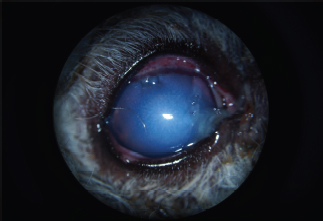

The responses to visual tests were positive on the left. The menace response was positive on the right, while the dazzle reflex was variable and difficult to interpret as a result of eye pain due to blepharospasm of moderate intensity. The left eye examination did not reveal any abnormalities. The right eye examination revealed the presence of sparse epiphora. A curvilinear, white, FB was present in the AC. Close examination with a biomicroscope revealed that it was a cat’s claw, for which the point of the corneal penetration was located in the upper quadrant. The latter was filled by a fibrin clot. Discrete corneal edema was present, as well as a uveal reaction manifested by tight myosis precluding observation of the lens (Fig. 1). The intraocular pressure was 7 mmHg, measured by rebound tonometry. Given the nature of the signs, FB extraction surgery was undertaken, associated with the perioperative exploration of the lens.

Fig. 1. Appearance of the eye at admission. Note the broken claw in the AC, corneal edema, fibrin clogging the entry point, and uveal reaction materialized by myosis.